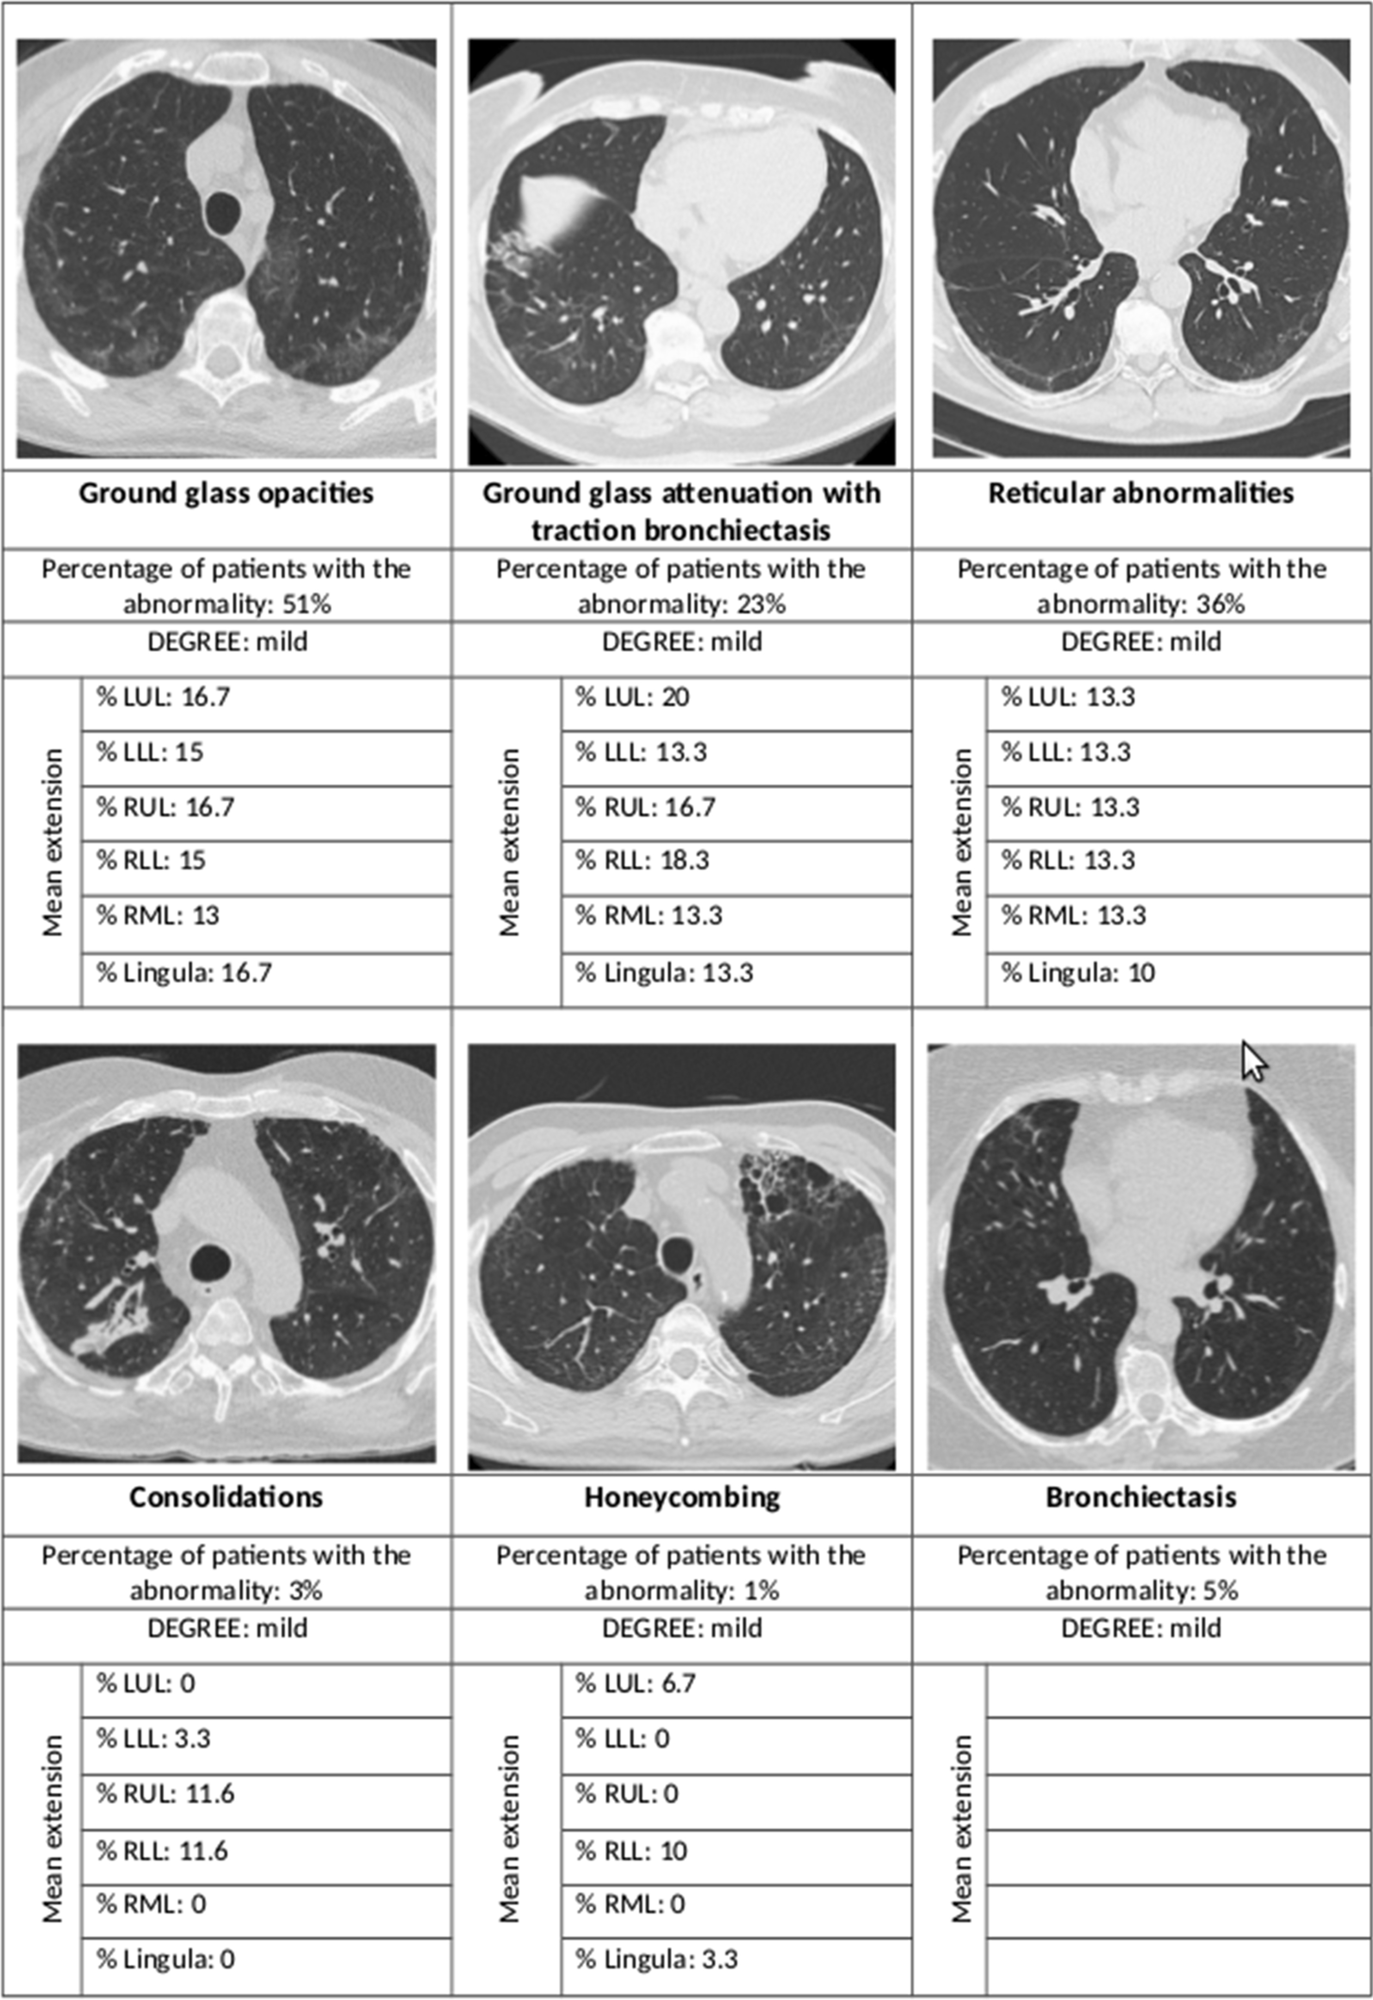

Summary of the main radiological abnormalities and their extension according to the lung lobe involved. LUL left upper lobe, LLL left lower lobe, RUL right upper lobe, RLL right lower lobe, RML right middle lobe

Most of the high-resolution CT (HRCT) scans showed interstitial lung changes; over half showed ground-glass opacities, over a third had reticular abnormalities, while less than 5% each showed consolidations and honeycombing. In 44% the ground glass opacities were accompanied by traction bronchiectasis or bronchiectasis.

The findings show that fibrosis of the lung is an uncommon finding after SARS-CoV-2 pneumonia requiring hospitalization, with only 1% of patients showing this complication at 12 months from discharge. Most cases showed other mild interstitial results, mostly ground-glass opacities and reticular abnormalities, mainly within a single lobe and limited in extent.